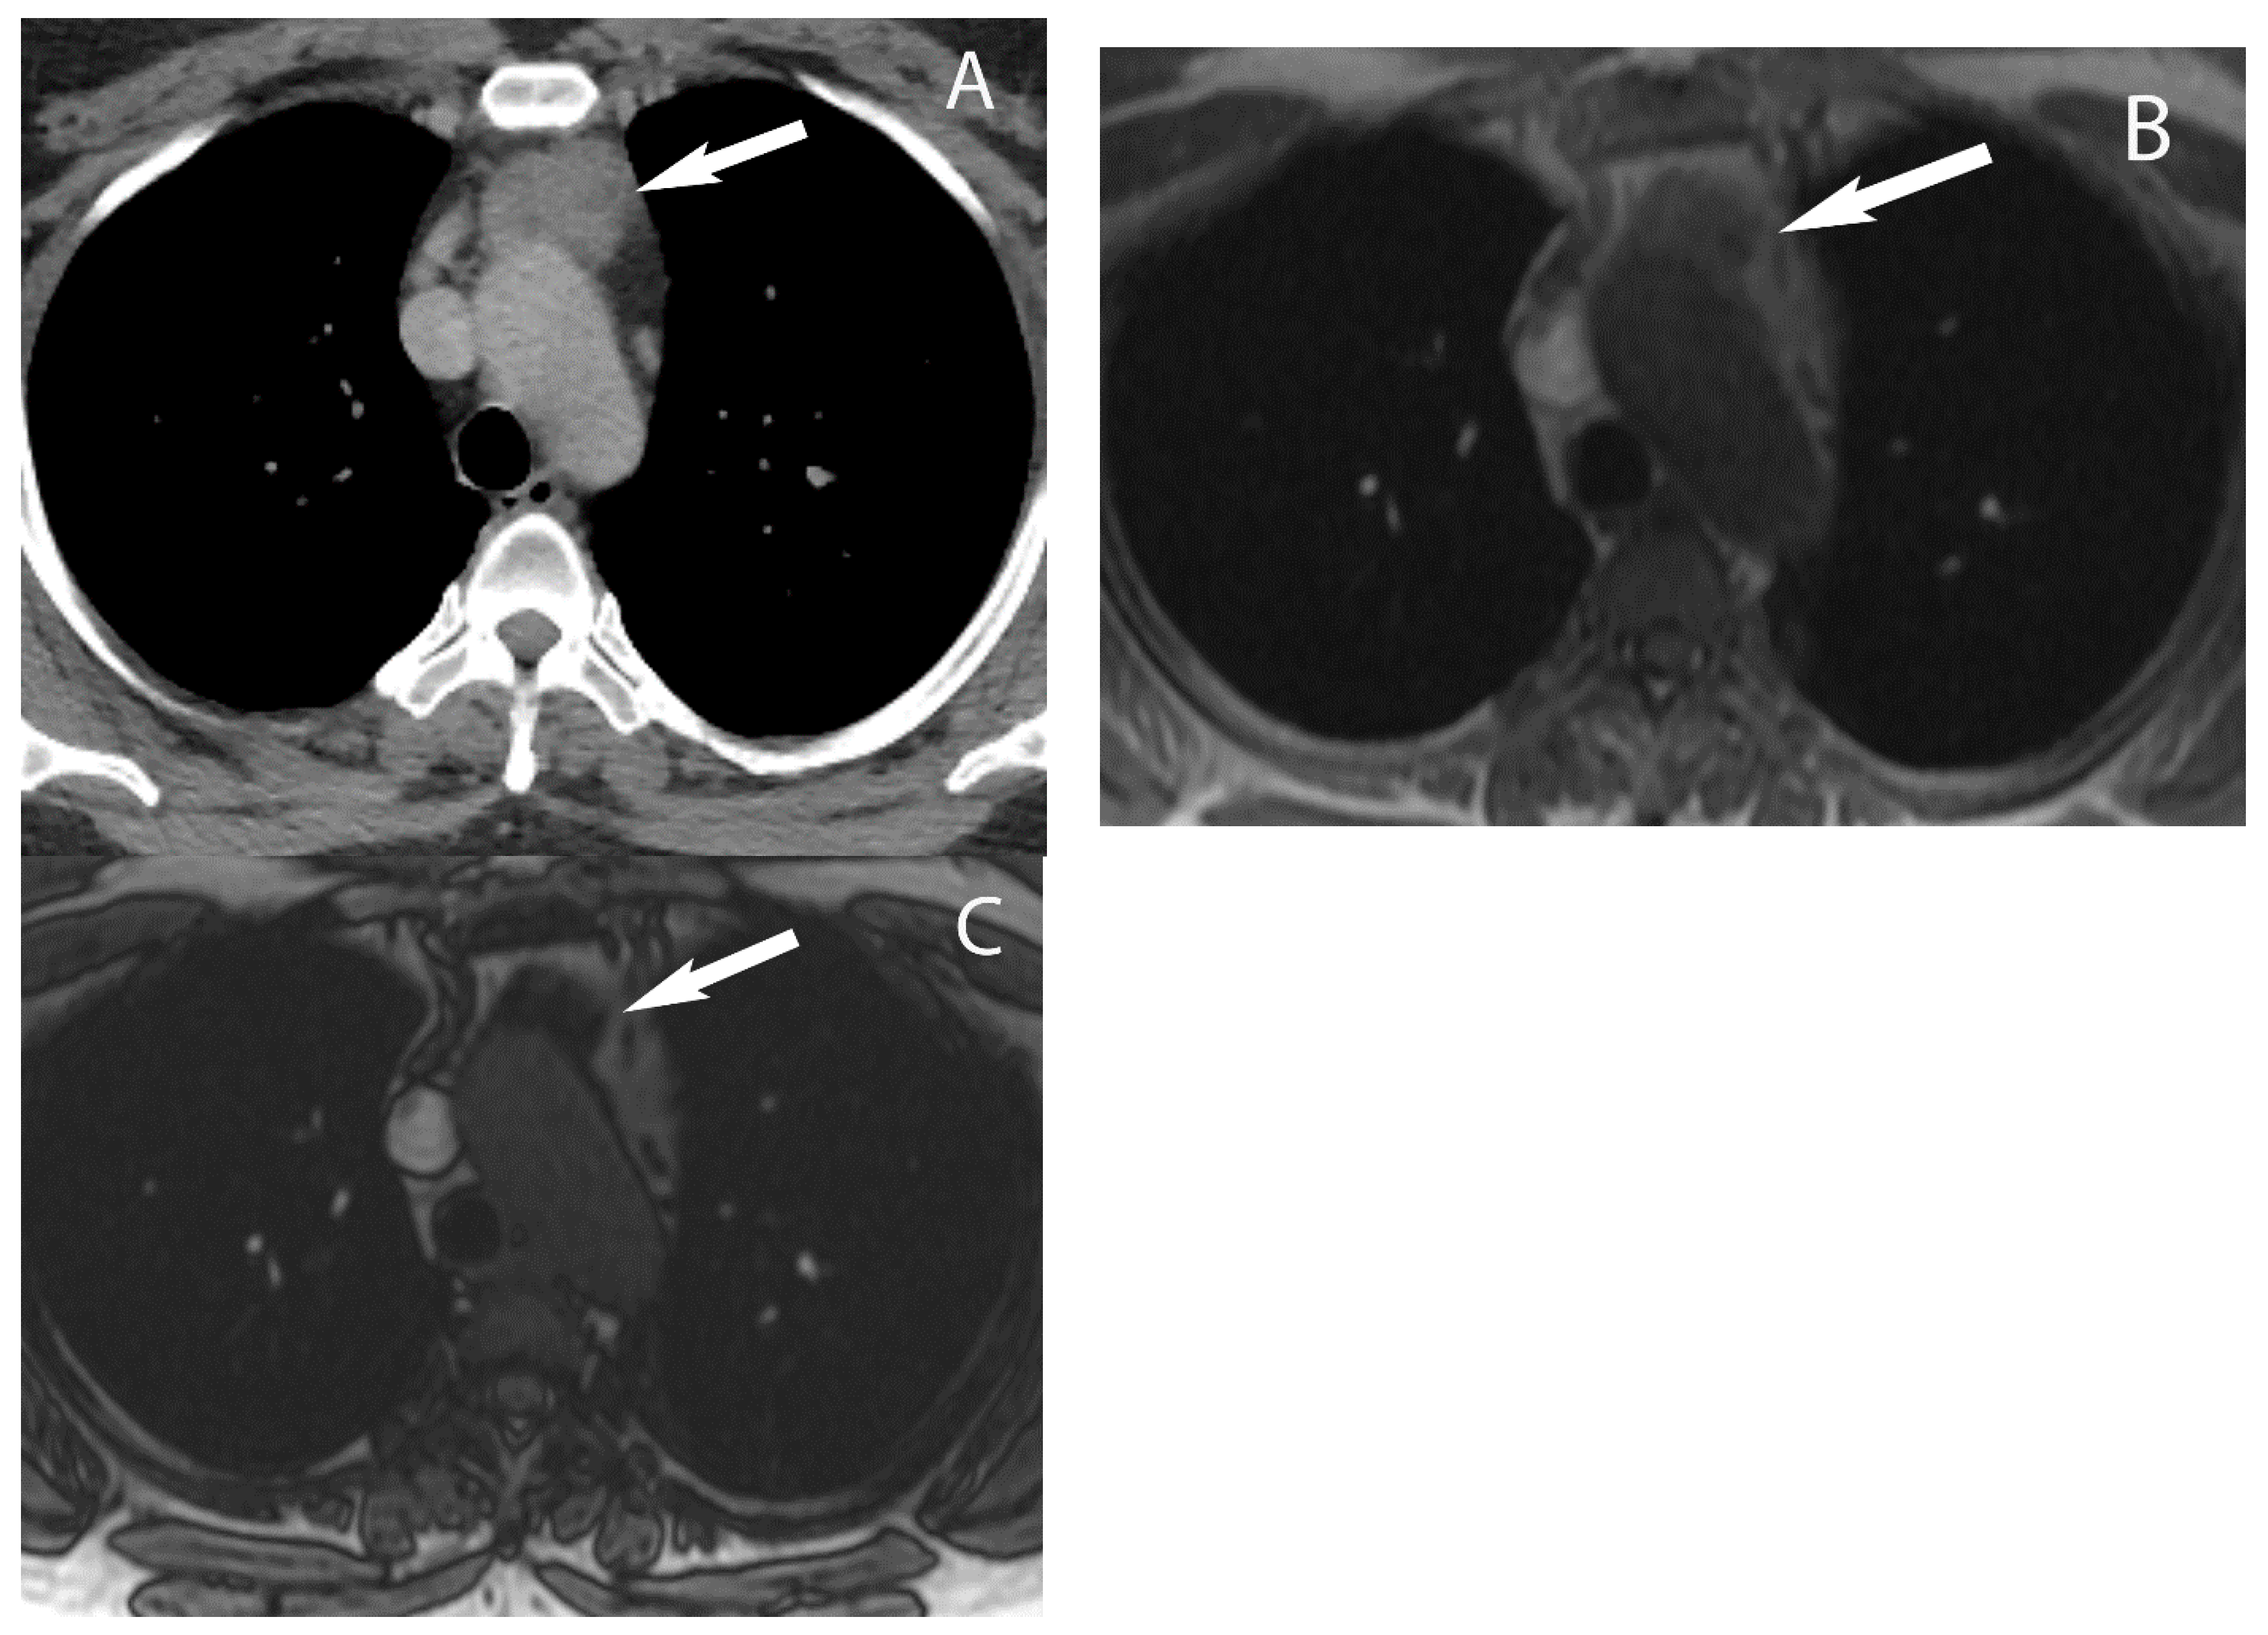

3. Cystic Lesions

6. Lymphoma

8. Cystic Lesions